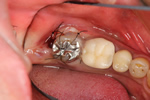

治療開始

抜歯と同時に、隣にある親知らず(横向きになっている歯)を移植しました。 動かないようワイヤーにて固定しています。

移植のために抜歯した親知らずです。